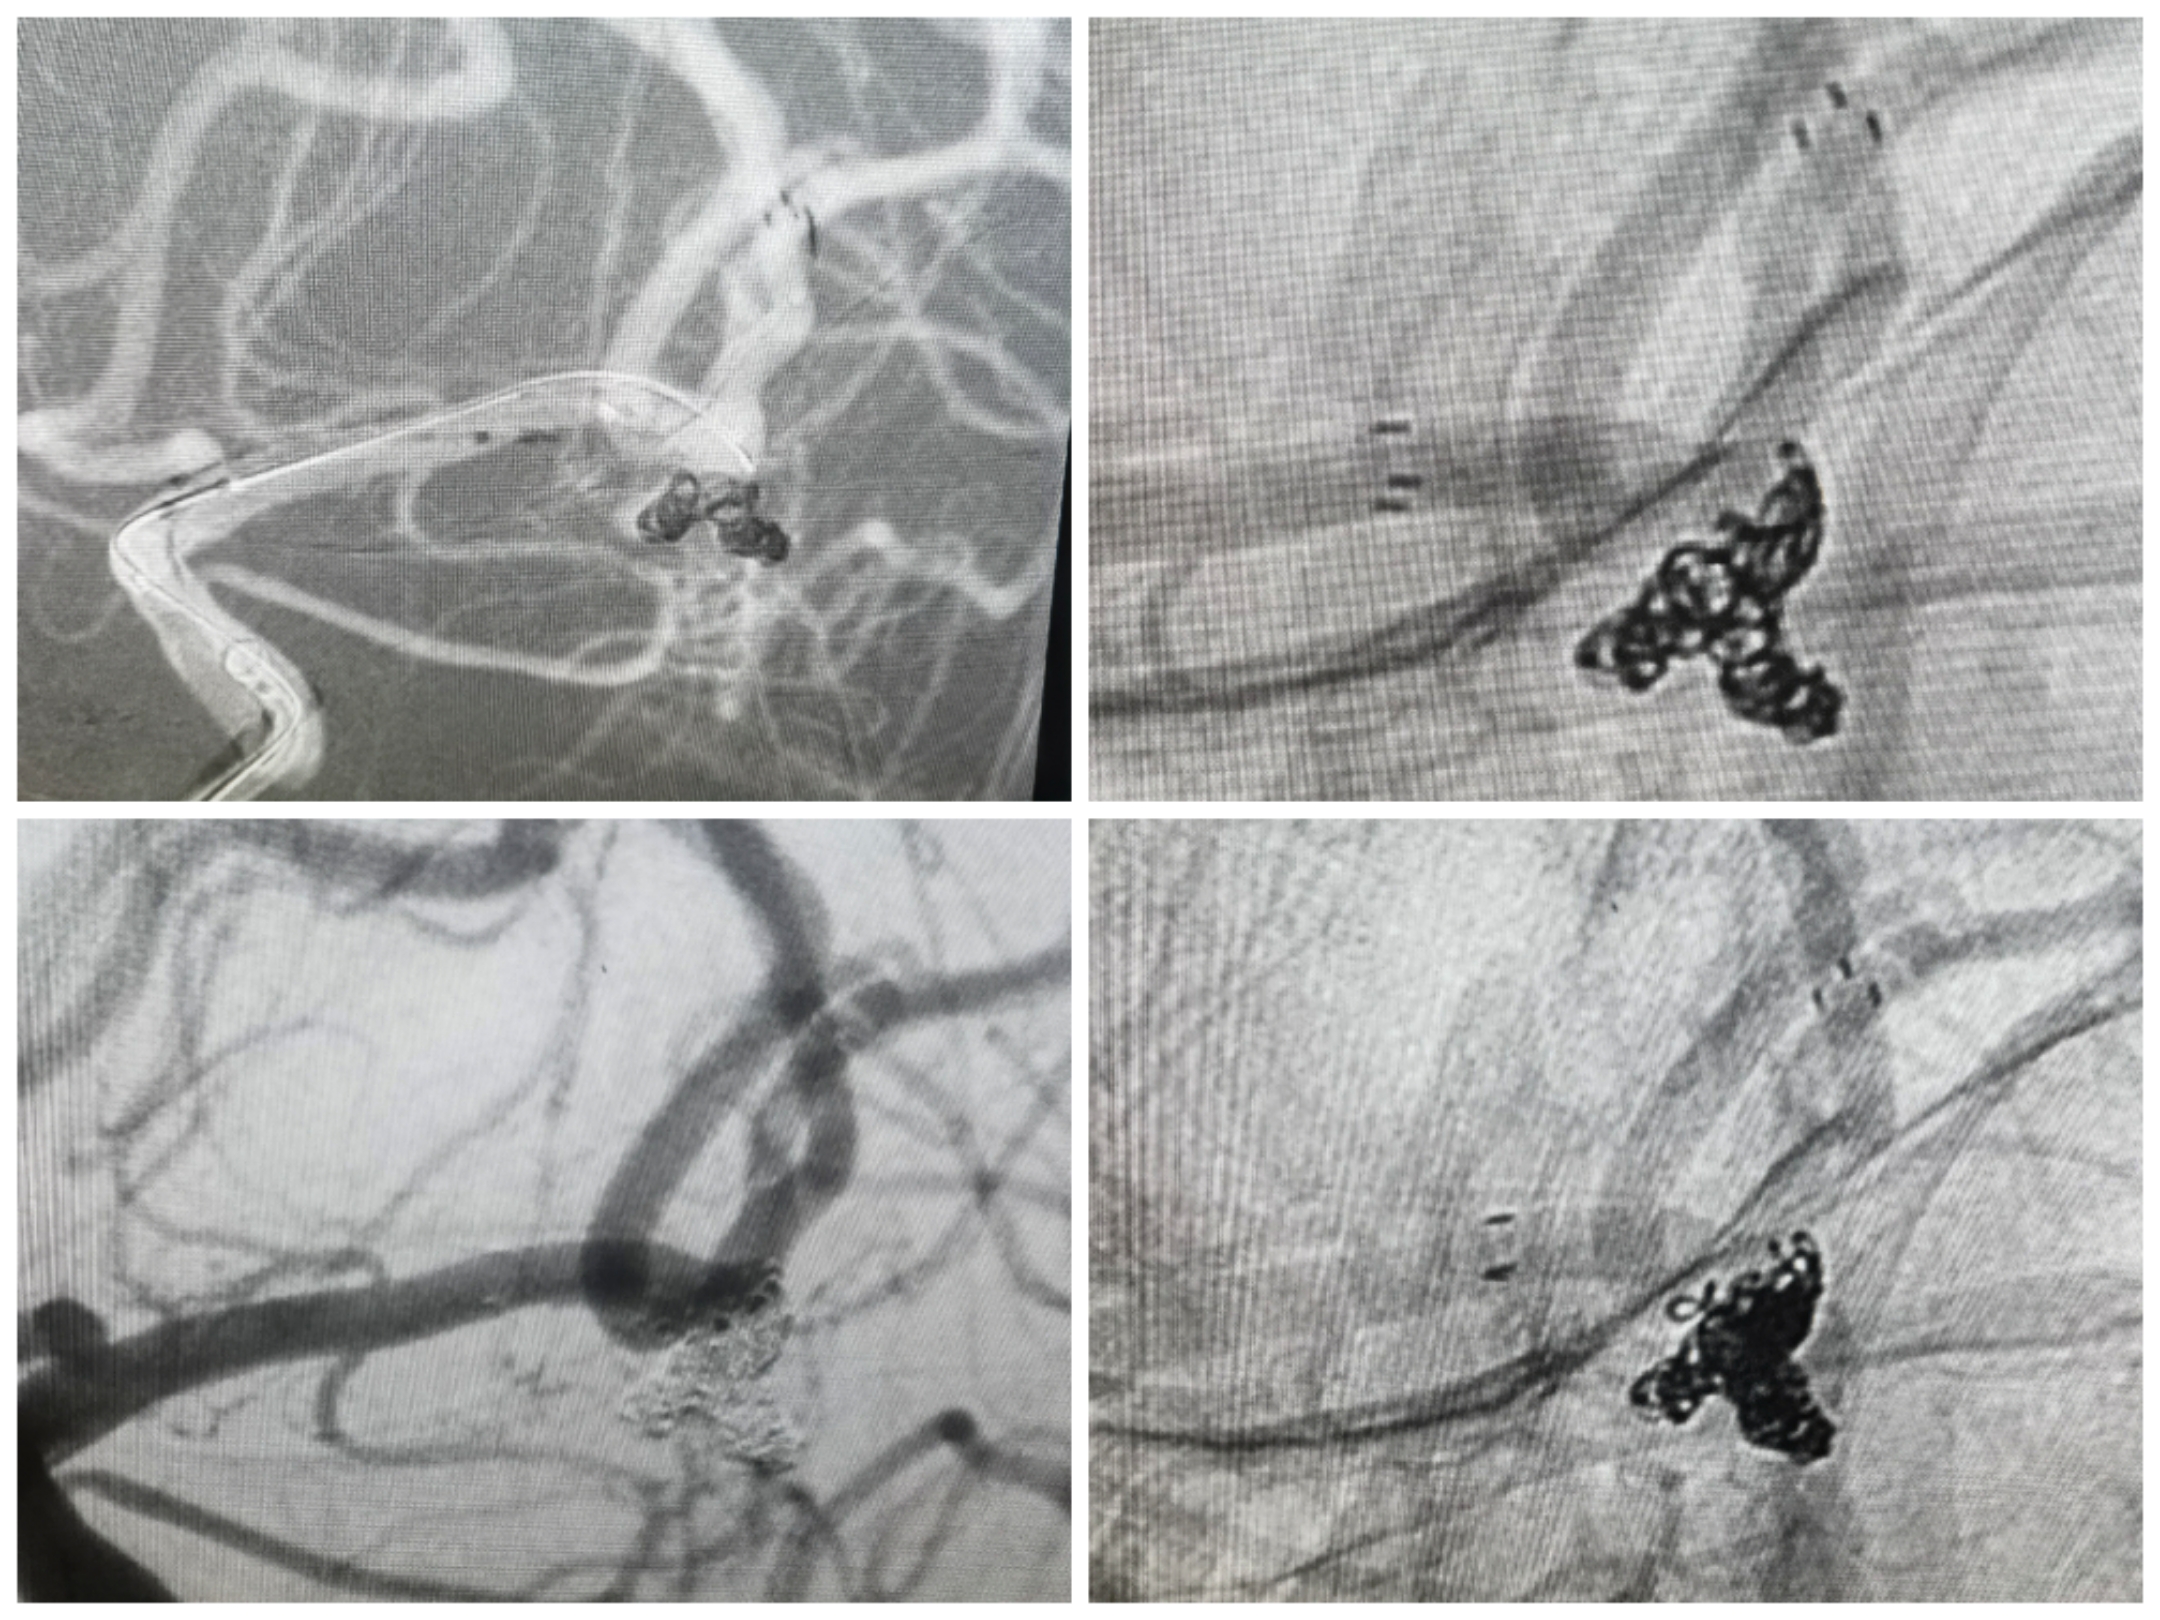

手术过程微导管布局情况:三系统栓塞,支架导管置于上干,两条微导管分别置于主囊和子囊中。

手术过程:先栓塞子囊,释放Atlas支架后甩尾(头端置于上干、尾端甩尾释放于下干开口保护两个干),后栓塞主囊

栓塞术后情况:支架甩尾保护双干,子囊及主囊栓塞完全

工作位,支架导管+双微导管到位情况

栓塞过程:双微管分区栓塞

栓塞术后情况

拟支架辅助+双微管栓塞,微导管布局情况

先栓塞远端子囊+支架释放,双微管交替栓塞